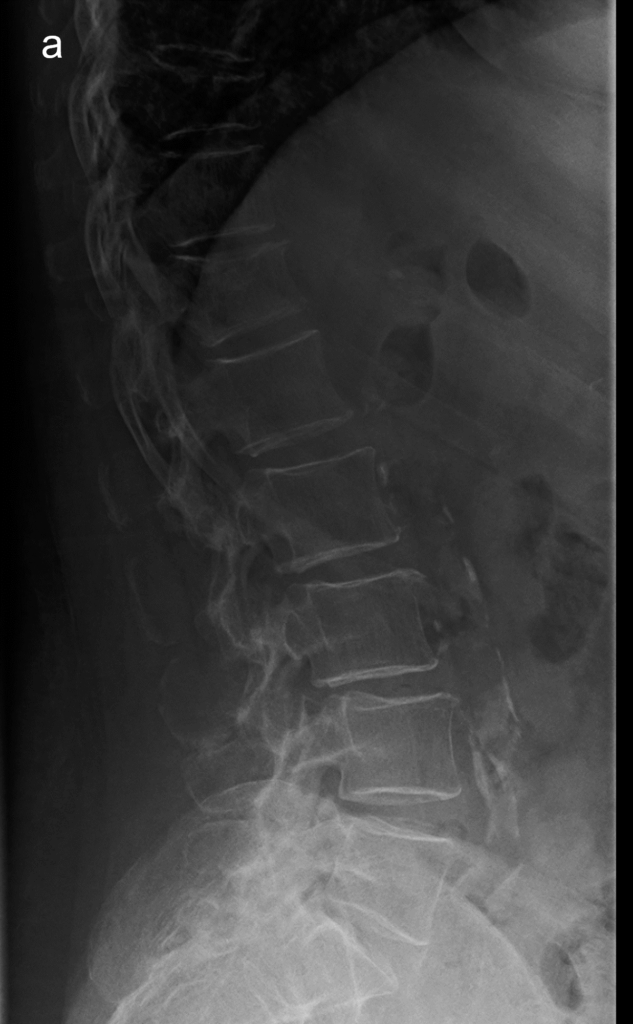

Il radiologo o l’operatore specializzato esamina le vertebre da T4 a L4 e assegna a ciascuna un punteggio di gravità basato sulla riduzione percentuale dell’altezza vertebrale rispetto all’altezza di riferimento (solitamente l’altezza posteriore della stessa vertebra o l’altezza di una vertebra adiacente sana).

La misurazione quantitativa computerizzata automatizza questo processo posizionando sei punti (reperi) su ogni corpo vertebrale, calcolando istantaneamente i rapporti tra le altezze anteriore, centrale e posteriore.

Sebbene la misurazione automatica sia rapida, la supervisione del radiologo è indispensabile per confermare la natura osteoporotica della deformità e non confonderla con varianti anatomiche o processi degenerativi.

Oltre alla misurazione geometrica, la diagnosi accurata si avvale di segni qualitativi che confermano la fragilità dell’osso:

- segno dell’angiomatosi: caratterizzato dalla perdita delle trabecole orizzontali con rinforzo di quelle verticali residue, che appaiono come linee striate verticali;

- segno della scatola vuota (empty box sign): le limitanti somatiche superiore e inferiore appaiono marcatamente accentuate e radiopache rispetto alla rarefazione del contenuto interno del soma vertebrale;

- interruzione della corticale: la presenza di scalini o interruzioni nella continuità della limitante anteriore o superiore è un segno quasi certo di frattura acuta o subacuta.9